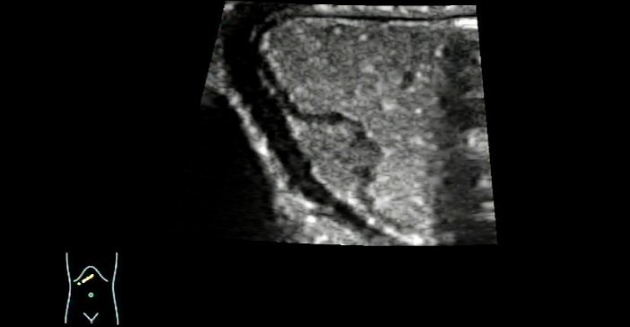

The patient underwent ultrasound examination after drinking 500 mL of contrast agent (instant gastrointestinal ultrasound aid) in a fasted state. The gastric wall featured a clear well-layered structure and a lack of mucosal smoothness, and a moderately hypoechoic mass of about 1.36 cm √ó 0.87 cm in size was detected in the submucosal layer of the lesser curvature of the gastric antrum. The mass was ovoid with clear margins, a broad base, and a continuous mucosal surface.

?

Moreover, a shallow depression was spotted in the center of the mass, with uneven echogenicity inside the mass (Figure 3).